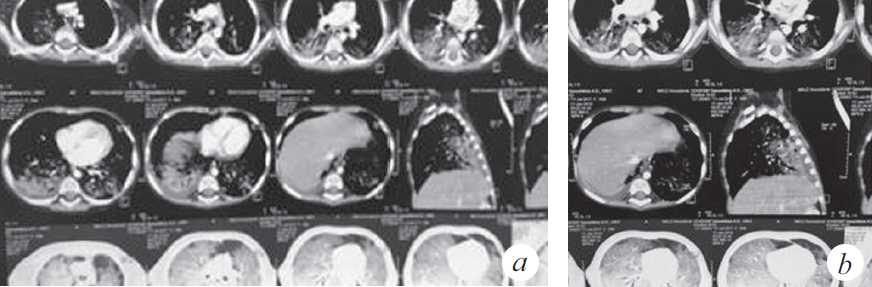

Через 2 нед. госпитализации в ОРИТ у ребенка наросли клинические и параклинические проявления госпитальной пневмонии (лихорадка, повышение С-реактивного белка до 39,7 мг/л), высев грибов рода Candida, Staphylococcus aureus — из верхних дыхательных путей; Еnterococcus faecalis, Еnterococcus fecuim, Klebsiella pneumoniae — из мочи, кала. На контрольной КТ: отрицательная динамика в виде увеличения консолидации в периферических отделах легких (рис. 2), клиническая картина не изменилась. На фоне антибактериальной терапии широкого спектра действия дыхательная недостаточность не прогрессировала, явления инфекционного токсикоза были купированы, кашель отсутствовал. Максимальная оценка по шкале SOFA (Sequential Organ Failure Assessment) 3 балла.

Рис. 2. Компьютерная томограмма органов грудной клетки (через 5 нед. от дебюта заболевания) (a). Признаки диффузного интерстициального повреждения легких. Отмечена отрицательная динамика в виде увеличения консолидации в периферических отделах легких (b)

Fig. 2. CT of the chest organs (5 weeks after the onset of the disease) (a). Signs of diffuse interstitial lung disease. Negative dynamics in the form of increased consolidation in the peripheral parts of the lungs (b)